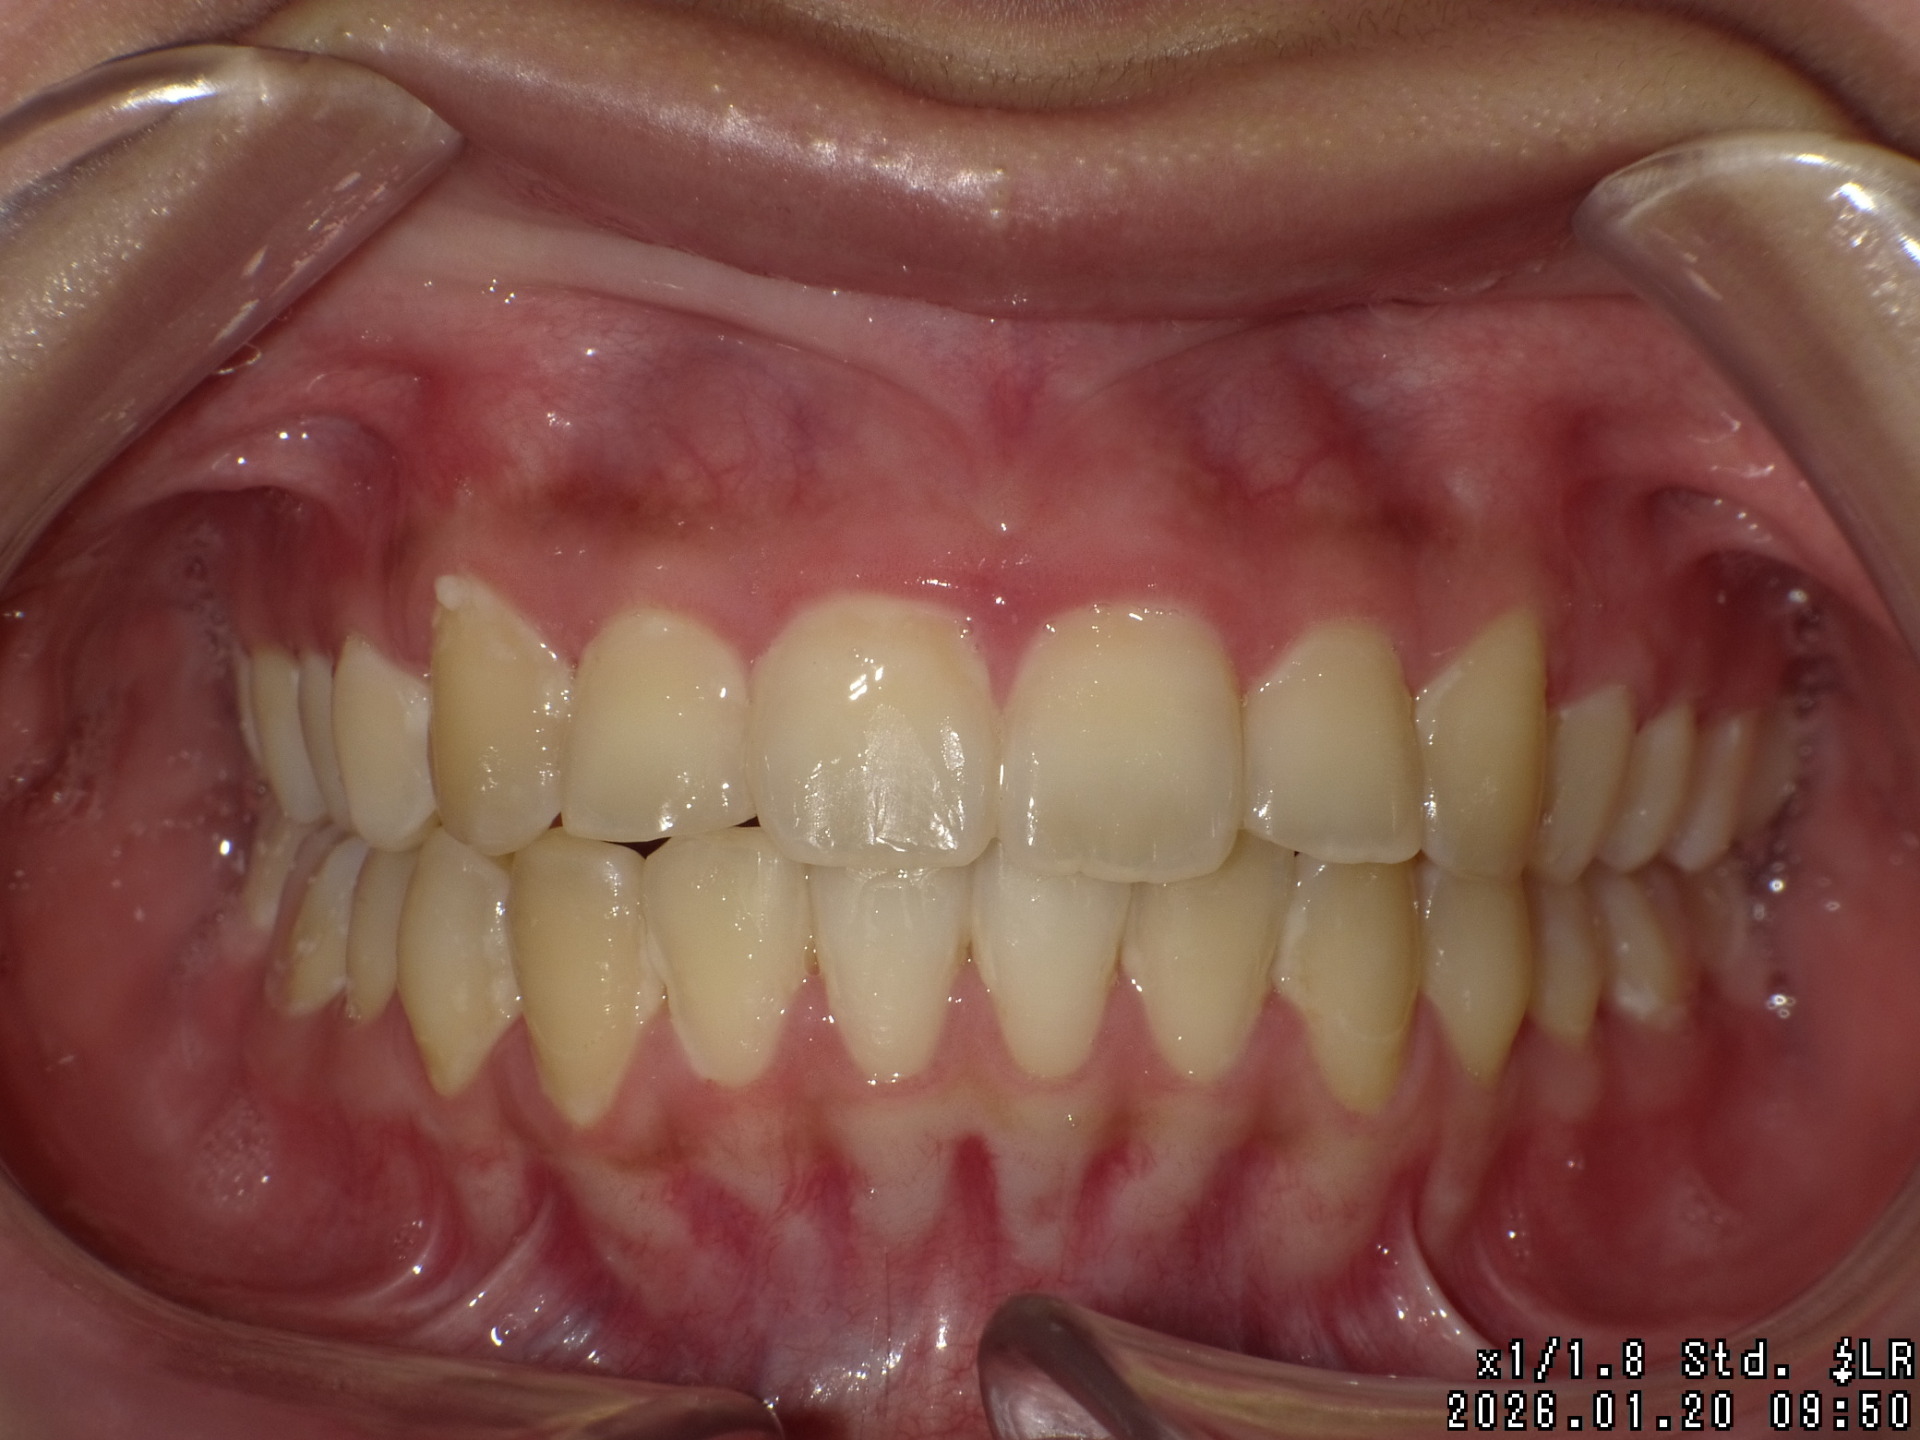

矯正後

| 症状 | 上顎前突 |

| 通院目的 | 永久歯を抜かずに歯並びを治したい。 |

| 処置内容 | バイトブロック・プレート拡大処置・クリアアライナー・マルチブラケット装置・プレート拡大付き切歯斜面板・SHA・ディスタライザー・インビザライン |

| デメリット・院長コメント | 永久歯を抜かない治療のデメリットは、治療期間が長いことです。 ただし、その後の人生の長さを考えると、健全な小臼歯を2本または4本抜歯の矯正治療よりも、はるかにメリットがあるといえます。 また、アーチが小さくならないので、舌が後ろに押し込まれないためいびき防止につながり睡眠の質の向上にもつながります。 |